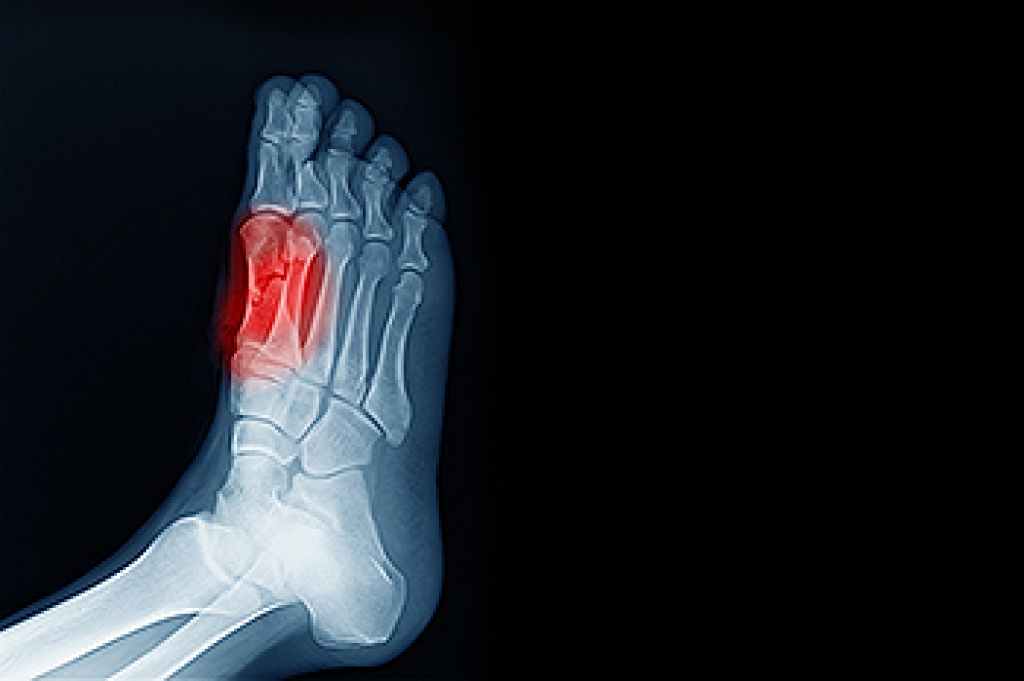

Gout is a form of arthritis that occurs when uric acid builds up in the blood, forming crystals in the joints. This leads to sudden, severe pain and inflammation, often affecting the big toe. The condition typically arises due to factors like a diet high in purines, obesity, dehydration, or kidney problems that prevent the proper excretion of uric acid. Symptoms of gout include intense joint pain, redness, swelling, and warmth in the affected area. The pain often comes on suddenly and can last for several hours or days. While gout can affect various joints, it most commonly targets the feet and ankles, especially the big toe. If you have developed this painful condition, it is suggested that you promptly consult a podiatrist who can offer appropriate treatment and management solutions.

Gout is a form of arthritis that is characterized by sudden, severe attacks of pain, redness, and tenderness in the joints. The condition usually affects the joint at the base of the big toe. A gout attack can occur at any random time, such as the middle of the night while you are asleep.